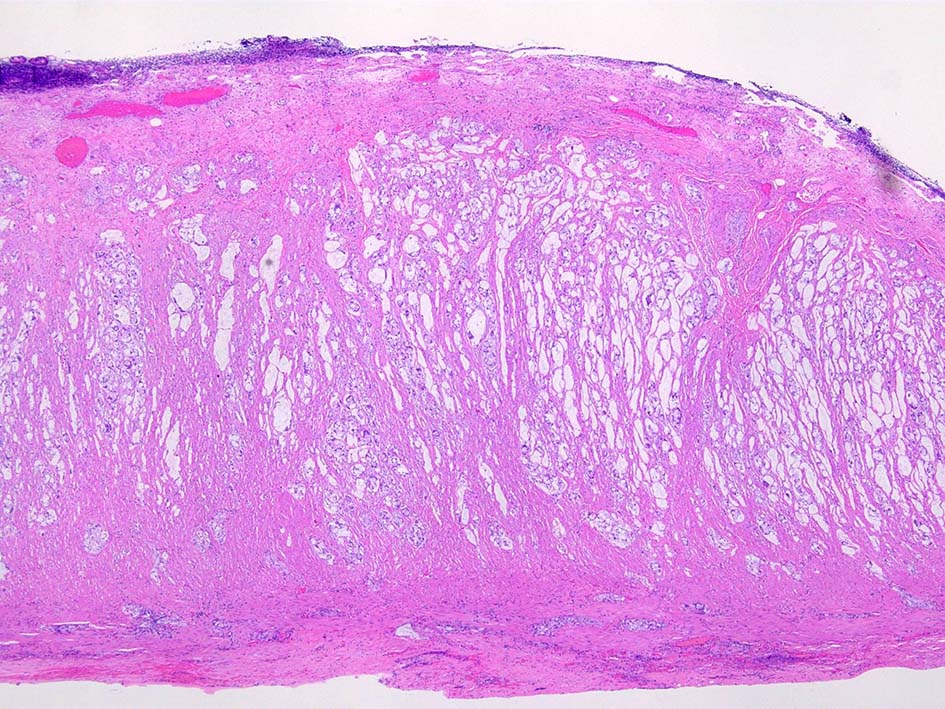

組織所見